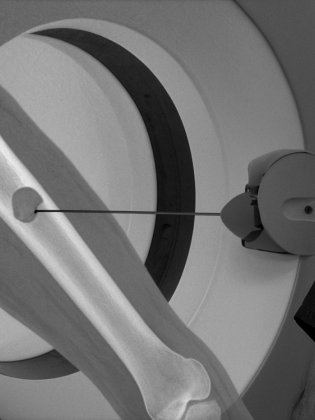

Ce geste est réalisé sous contrôle d’imagerie (scanner, cone-beam CT, IRM ou radiographie) à l’aide d’une fine aiguille introduite à travers la peau, sans incision chirurgicale.

Une fine aiguille est introduite sous guidage image jusqu’au kyste. Le produit sclérosant est injecté directement dans la cavité osseuse. Le geste dure en moyenne 30 à 60 minutes.